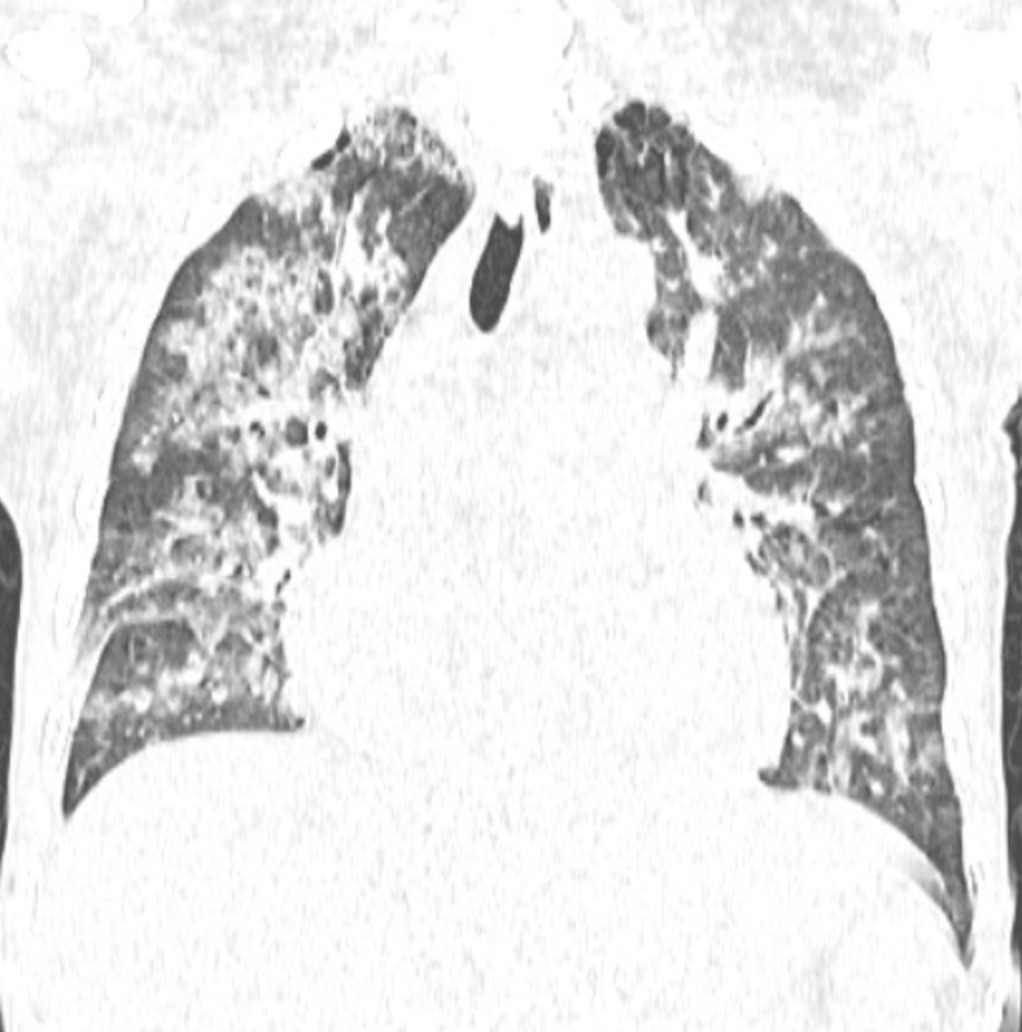

Phim chụp Xquang phổi của bệnh nhân C.Đ.C (21/10) - Ảnh BVCC

Vào viện, người bệnh được làm xét nghiệm máu và tủy, được chẩn đoán Bệnh bạch cầu cấp dòng tủy (AML-M6) kèm nhiễm trùng tiết niệu, rối loạn đông máu. X-quang ngực chụp buổi sáng cho thấy hai trường phổi sạch, tràn dịch màng phổi nhẹ, nghĩa là phổi lúc đó hoàn toàn “trong”.

Phim chụp Xquang phổi của bệnh nhân C.Đ.C (24/10) - Ảnh BVCC